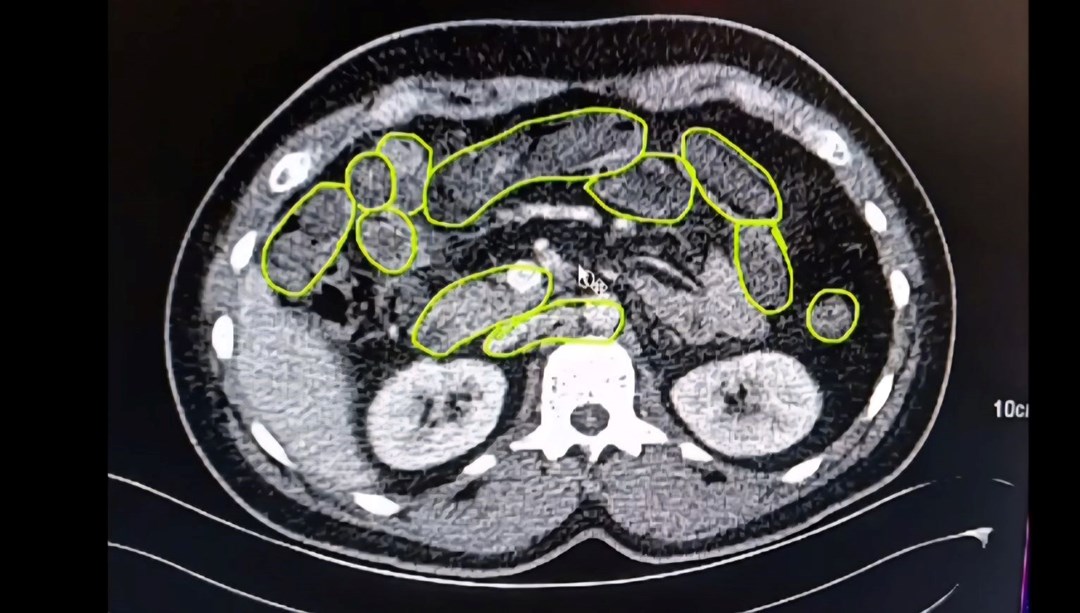

Röntgen ve ultrason sonrası kontrollerde 3 şüphelinin midesinde uyuşturucu madde olduğu belirlendi.

Şüphelilerin yuttukları uyuşturucuları kente sokmaya çalıştıkları tespit edildi. Kapsüller, sağlık ekibinin müdahalesiyle çıkarıldı. Taburcu edilen şüpheliler, İlçe Jandarma Komutanlığı’na götürüldü.